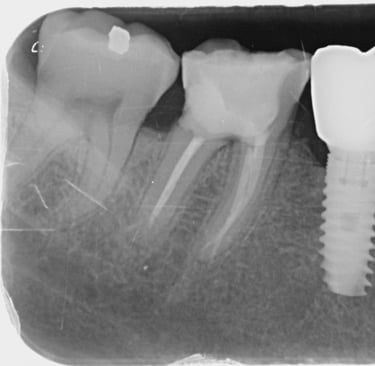

En otros casos, puede ser necesario tomar una radiografía que abarque todo el diente. Estas radiografías se pueden utilizar, por ejemplo, para detectar caries o inflamación en el ápice de la raíz. Se toman, por ejemplo, antes de colocar una corona o en relación con un tratamiento de conducto.